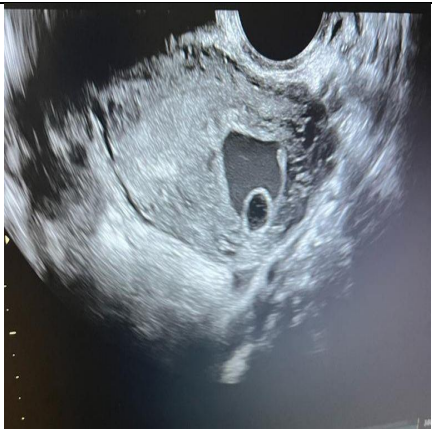

A 16-year-old lady, para 0+2 presented to the emergency department complaining of active vaginal bleeding after medical treatment of missed miscarriage. She had history of two recurrent miscarriages treated by surgical evacuation. Her pregnancy was spontaneous. Her medical history was unremarkable. Clinically she was vitally stable, soft abdomen, no tenderness no palpable masses. Speculum examination was suggestive of normal-looking cervix with bleeding from the os, uniformly enlarged 8 weeks size uterus freely mobile, no cervical movement tenderness, and no adnexal masses. An ultrasound demonstrated a gestational sac about 2.2 cm in diameter. It showed also a yolk sac and a fetal pole of 8 mm without cardiac cavity. Surgical suction and evacuation was performed under ultrasound guidance.  During the evacuation, the gestational sac was noted to be below the suction tube, the procedure was aborted. The intrauterine products were sent for histology which showed fragments of endometrium, blood clots and fibrosed chorionic villi, no evidence of malignancy. Upon reassessment, she was still complaining of the vaginal bleeding. Beta human chorionic gonadotropin was 1450. A Trans abdominal & trans vaginal ultrasound scan showed empty cavity with thick endometrium, a gestational sac below the line of endometrium with a yolk sac and fetal pole without cardiac activity, embedded in the myometrium (Fig.1&2&3&4) .The use of 3-D ultrasound helped in confirming the diagnosis of intramyometrial pregnancy, providing highly informative and detailed imaging to support accurate clinical assessment (Fig.5&6). In view of her parity and future fertility medical treatment was discussed with and accepted by the patient. Methotrexate was administered with a single dose of 50mg given intramuscularly on day 7, the drop was less than 15%. The patient received a second dose of methotrexate .The patient was displaced due to war circumstances. She then continued to have serial pregnancy tests, not able to have quantitative B-HCG test. Her pregnancy test became negative eventually then her menstrual cycle resumed back with regular intervals.

FIG.1

Figure 1